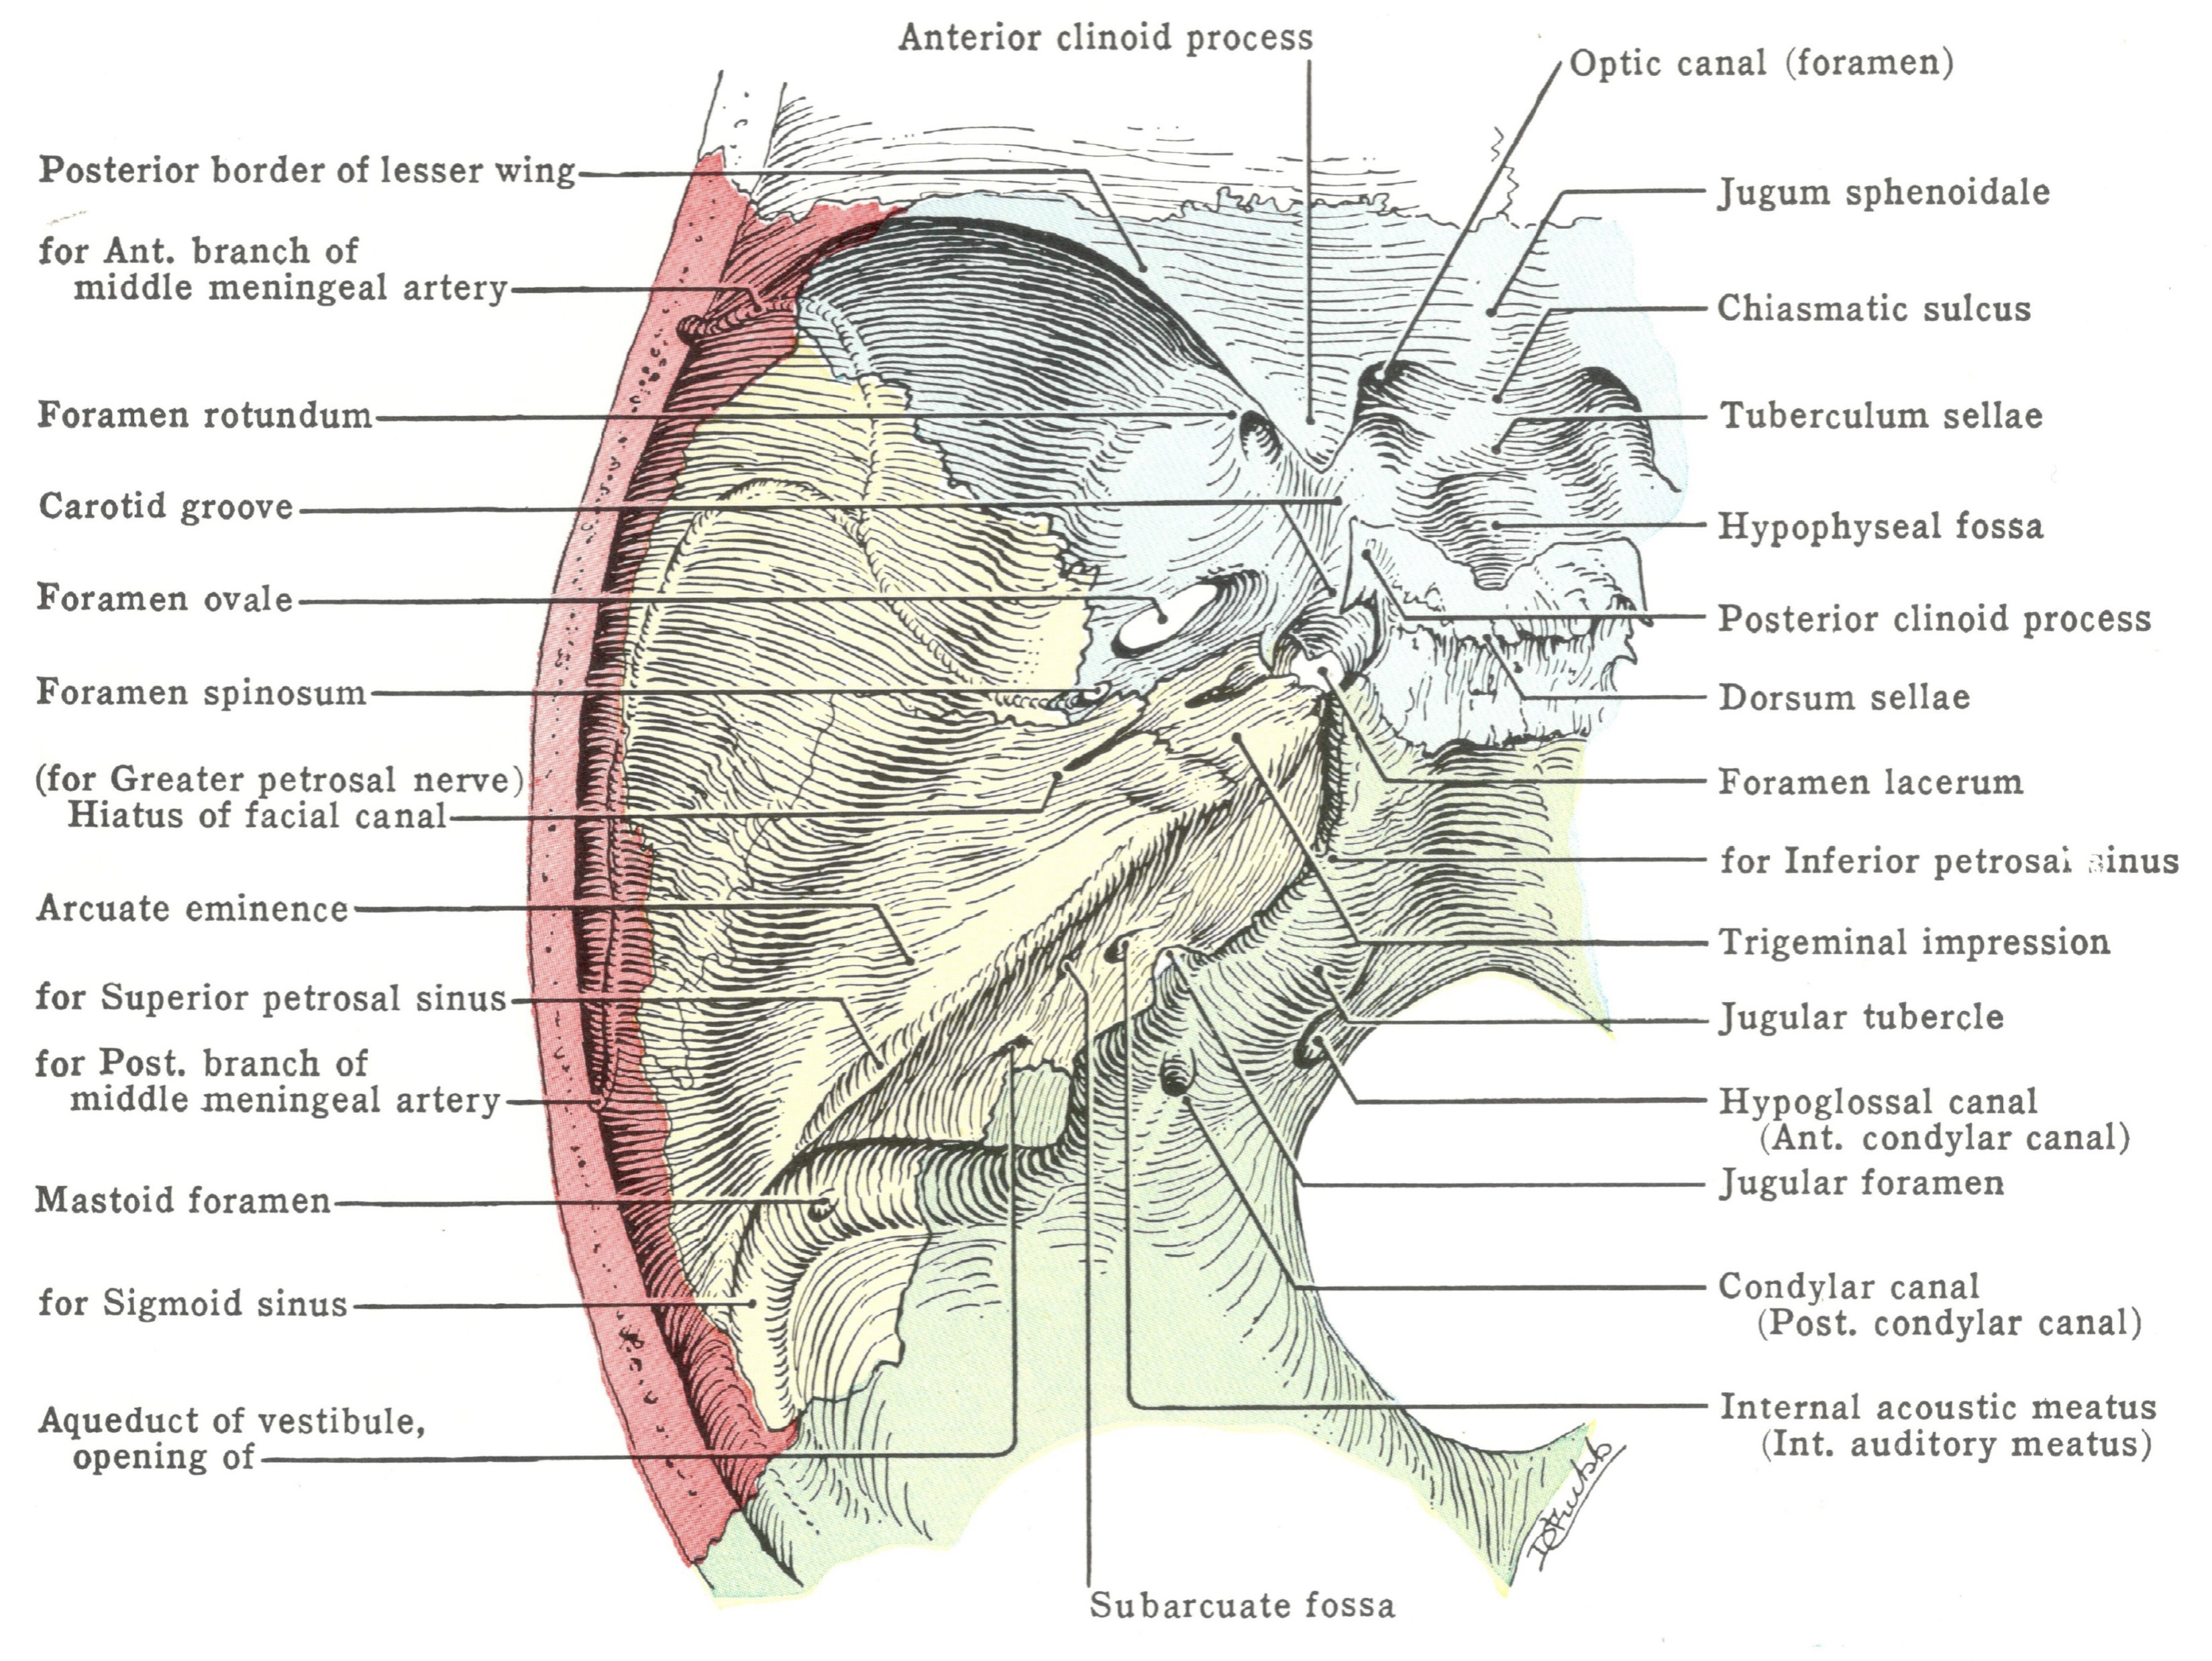

| CN | Origin | foramen |

|---|---|---|

| I | 嗅球 | cribriform plate |

| II | Optic Chiasma | optic canal |

| III, IV | Midbrain | sup orbital fissure |

| V1, VI | pons | |

| V2 | foramen rotundum | |

| V3 | foramen ovale | |

| VII | Internal coustic meatus | |

| VIII | Pons, Medulla 之間 | |

| IX, X, XI | Medulla | jugular foramen |

| XII | Hypoglossal canal |

Sphenoid bone

Foramen rotundum

Foramen ovale

Foramen spinosum

Foramen lacerum (破裂孔)

Optic canal

Sup. orbital fissure

Temporal bone

- Carotid canal

- Ext. acoustic meatus

- Int. acoustic meatus

- CN VII, VIII

- Jugular foramen

- int. jugular v.

- CN IX, X, XI

- Stylomastoid foramen

Occipital bone

- Hypoglossal canal

- CN XII

- Foramen magnum

- Spinal cord

- Vertebral a.

- CN XI

- Jugular foramen